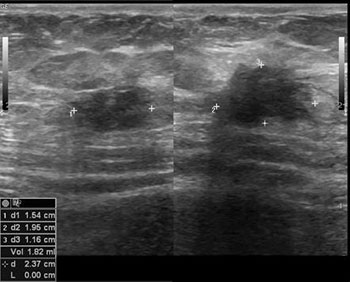

• Ultrasound scan: Helps detect a solid or cystic lesion within the scar tissue.